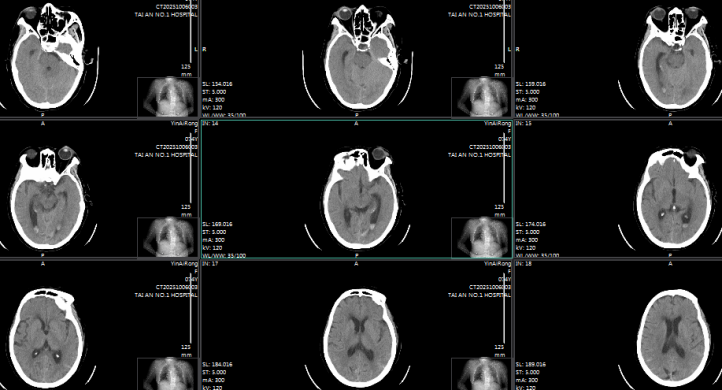

术前颅脑CT

术后7天颅脑CT

74 岁的女性患者,因 “头晕伴恶心、呕吐 2 小时余” 紧急入院,颅脑 CT 检查显示蛛网膜下腔出血,头颈部 CTA 提示高度可疑右侧小脑后下动脉动脉瘤。术中造影进一步明确,该动脉瘤位于右侧小脑后下动脉扁桃体延髓段,大小约 1.9mm×1.4mm,瘤颈 1.0mm,瘤顶指向前下方且可见子瘤,正是此次出血的 “责任动脉瘤”。